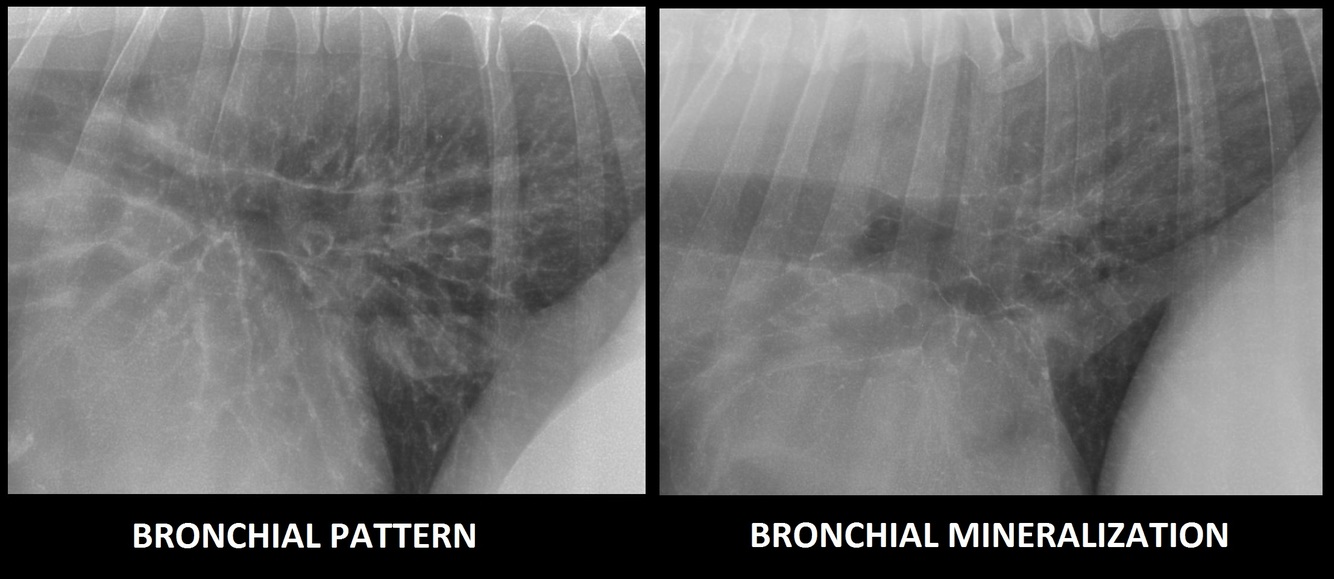

i. Classically see a bronchial pattern

ii. Characteristic “train tracks” and “doughnuts” which are thickened bronchial walls